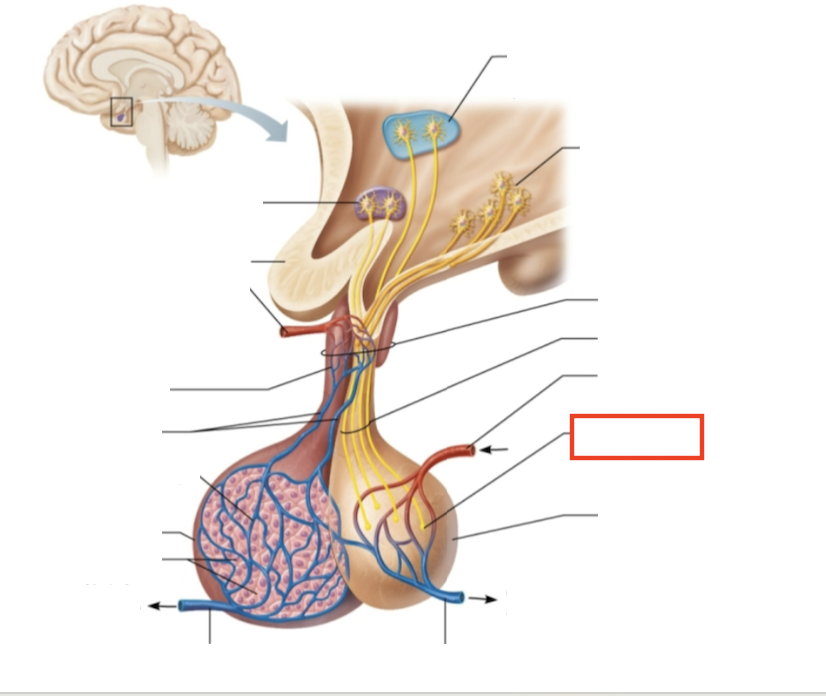

What structure is highlighted?

inferior hypophyseal artery

What structure is highlighted?

neurohypophysis (storage area for hypothalamic hormones)

What structure is highlighted?

posterior pituitary

What molecules are produced here?

oxytocin, ADH